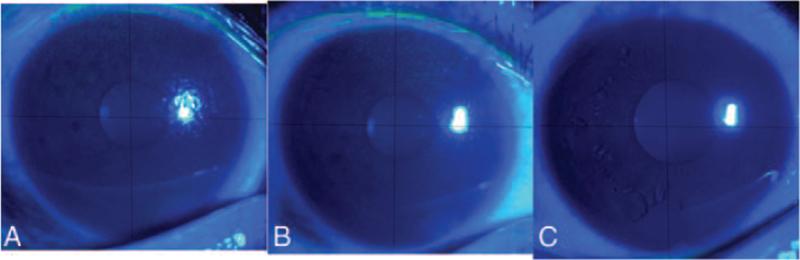

Changes of Ocular Surface Before and After Treatment of Blepharoptosis With Combined Fascial Sheath Suspension and Frontal Muscle Flap Suspension.

The patients were divided into group A and group B, Group A received conjoint fascial sheath suspension, and group B received frontal muscle flap suspension. The ocular surface changes were followed upon the 7th day and in the 1st and 3rd month after operation, which included Schirmer test (ST), break-up time (BUT), tear meniscus height (TMH). For normal distribution variables, t test was used before and after operation, and the Wilcoxon test was used for variables with abnormal distribution.

Compared to preoperative status, the ST and TMH were not significantly changed after surgery (P > 0.05), but BUT higher on the 7th day and in the 1st and 3rd month after operation (P < 0.05). The fluorescence staining (FL) score was higher in the 3rd month than that in the 1st month (P < 0.05), but was not significantly different between the 7th and in the 1st month after operation (P > 0.05). The ST, TMH, and BUT after surgery were not significantly different between groups of A and B (P > 0.05), but the FL score lower in the 3rd month than on the 7th day and in the 1st month after operation (P < 0.05).

The ST, BUT, and TMH were not significantly changed after surgery between groups of A and B, but the FL score was lower in group A than that in group B in early postoperative time.